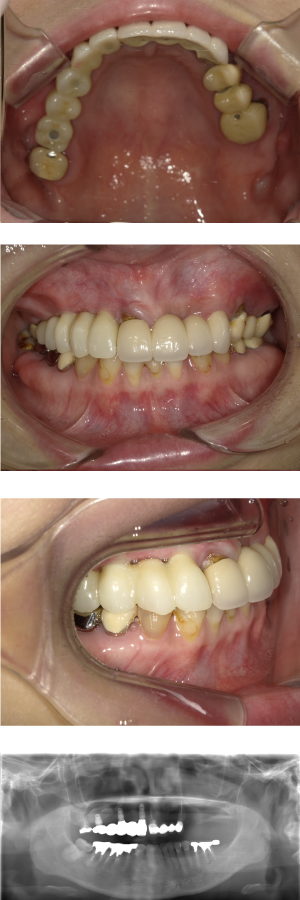

60代 女性 全顎 インプラント サイナスリフト等

| 年代・性別 | 60代・女性 |

| 主訴 | 上顎の入れ歯が割れた。リンゴやおかきを食べられるようになりたい。 |

| 部位 | 右上④3②・左上②3④5⑥のブリッジ |

| 治療期間 | 2年 |

| 費用 | ¥2,447,500(税込) |